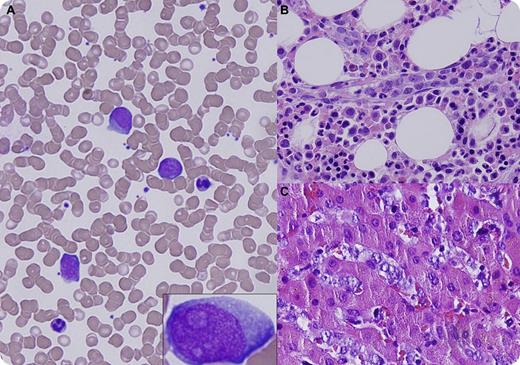

A 59-year-old man presented with acalculous cholecystitis and hepatomegaly. Routine laboratory tests were remarkable for thrombocytopenia (125 × 109/L), alanine aminotransferase 95 U/L, aspartate aminotransferase 760 U/L, alkaline phosphatase 223 U/L, and lactate dehydrogenase 3755 U/L. A peripheral smear showed morphologically normal red blood cells and large atypical lymphoid cells (panel A and inset). Cholecystectomy, liver biopsy, and bone marrow biopsy were performed. Flow cytometry on bone marrow and peripheral blood demonstrated a population of λ-restricted B cells that were positive for CD19, CD20, and CD22, and coexpressed CD5 and CD10. Histologic sections showed large atypical lymphoid cells within small subserosal vessels of the gallbladder, as well as within hepatic (panel C) and bone marrow sinusoids (panel B). Immunohistochemistry showed strong positivity for CD20, PAX-5, CD5, CD10, and Ki-67. Fluorescent in situ hybridization revealed a distal deletion of BCL6 and 3 to 5 copies of BCL2. Cerebrospinal fluid examination was unremarkable.

Intravascular large B-cell lymphoma (IVLBCL) is a rare subtype of extranodal large B-cell lymphoma characterized by intraluminal growth of lymphoma cells within small vessels. Circulating lymphoma cells in the peripheral blood happens occasionally. Once called the oncologist's “great imitator,” IVLBCL can mimic, because of its intrinsically widespread nature, diseases in almost any organ and diagnosis requires high vigilance.